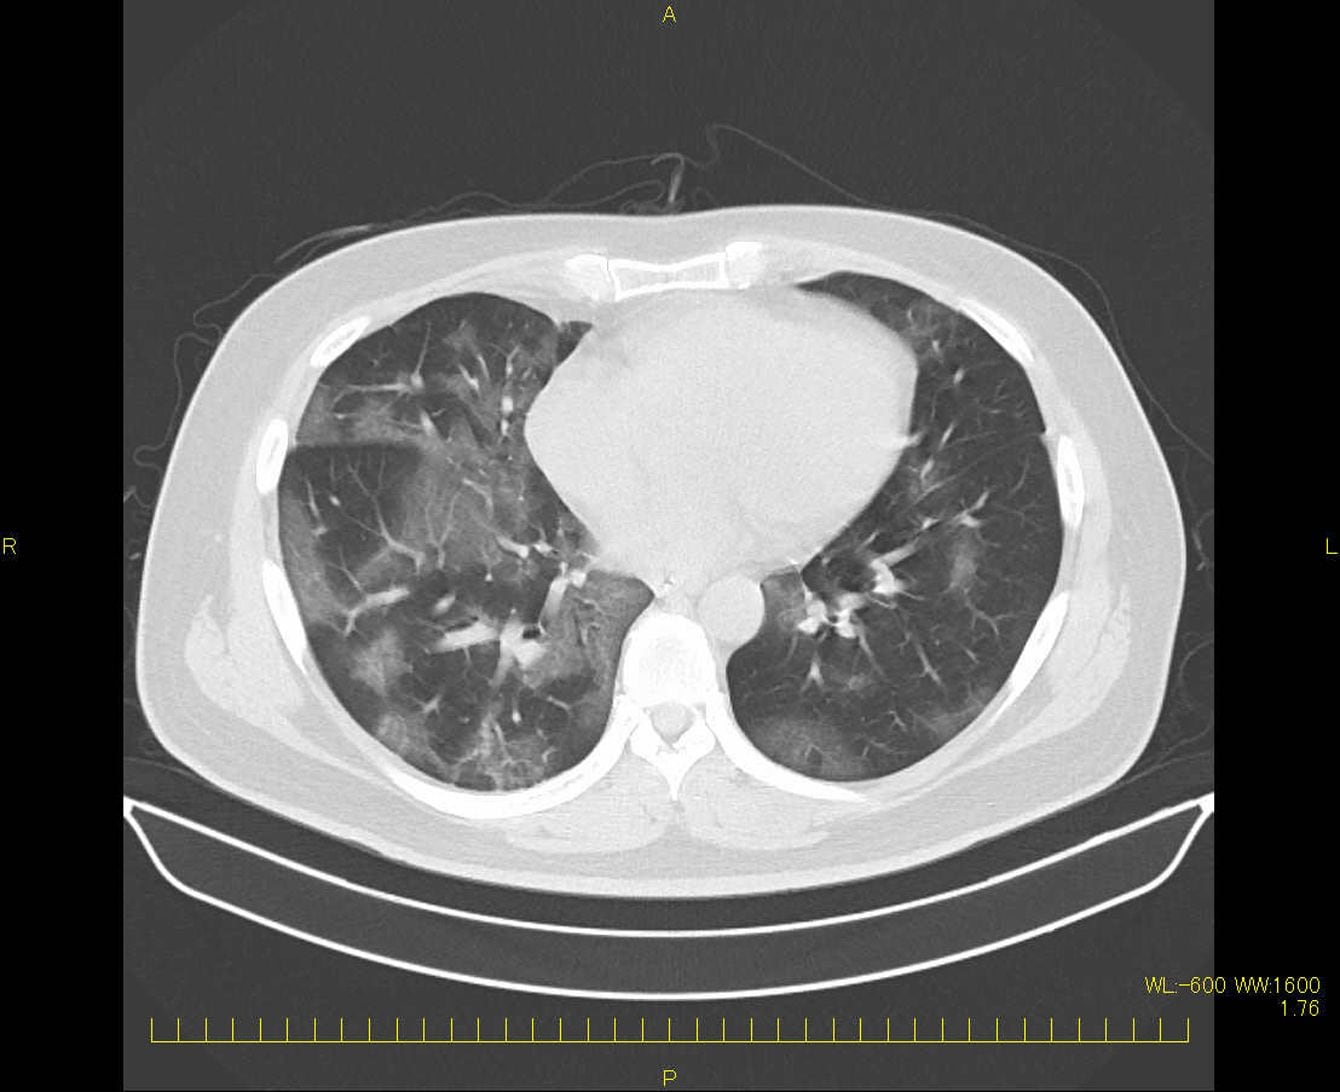

記憶が消えていく、夜眠れない、髪が抜け落ちる…特効薬のない「新型コロナ後遺症」を抱えて生きるリアル

新型コロナに感染した外科医の肺CT画像